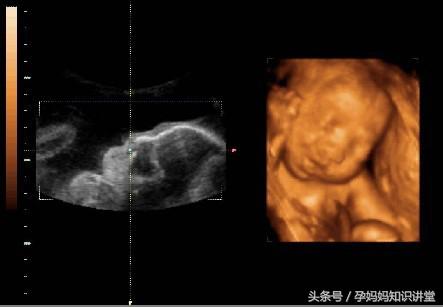

一、胎儿状况

1、体重:怀孕36周,孕妈的体重已经达到了最高峰,胎宝宝的身体发育已经基本完成了,体重已经有2.8千克了。

2、四肢:胎儿的四肢会在子宫里自由地活动,而且手指还能轻轻地碰到嘴唇,完成吮吸的动作。

3、骨骼:胎宝宝的骨骼基本发育成熟,已经相当的坚硬了。但是头盖骨的形状还不固定,在分娩的时候,为了顺利通过妈妈的产道,宝宝的头骨会发生变形,到产后几个月慢慢地孤星形状。

4、胎位:可能有些胎儿已经完成了入盆,将自己头部埋在妈妈的盆骨处,背部朝向妈妈的子宫,做出跃跃欲试的姿势,随时准备和妈妈见面。